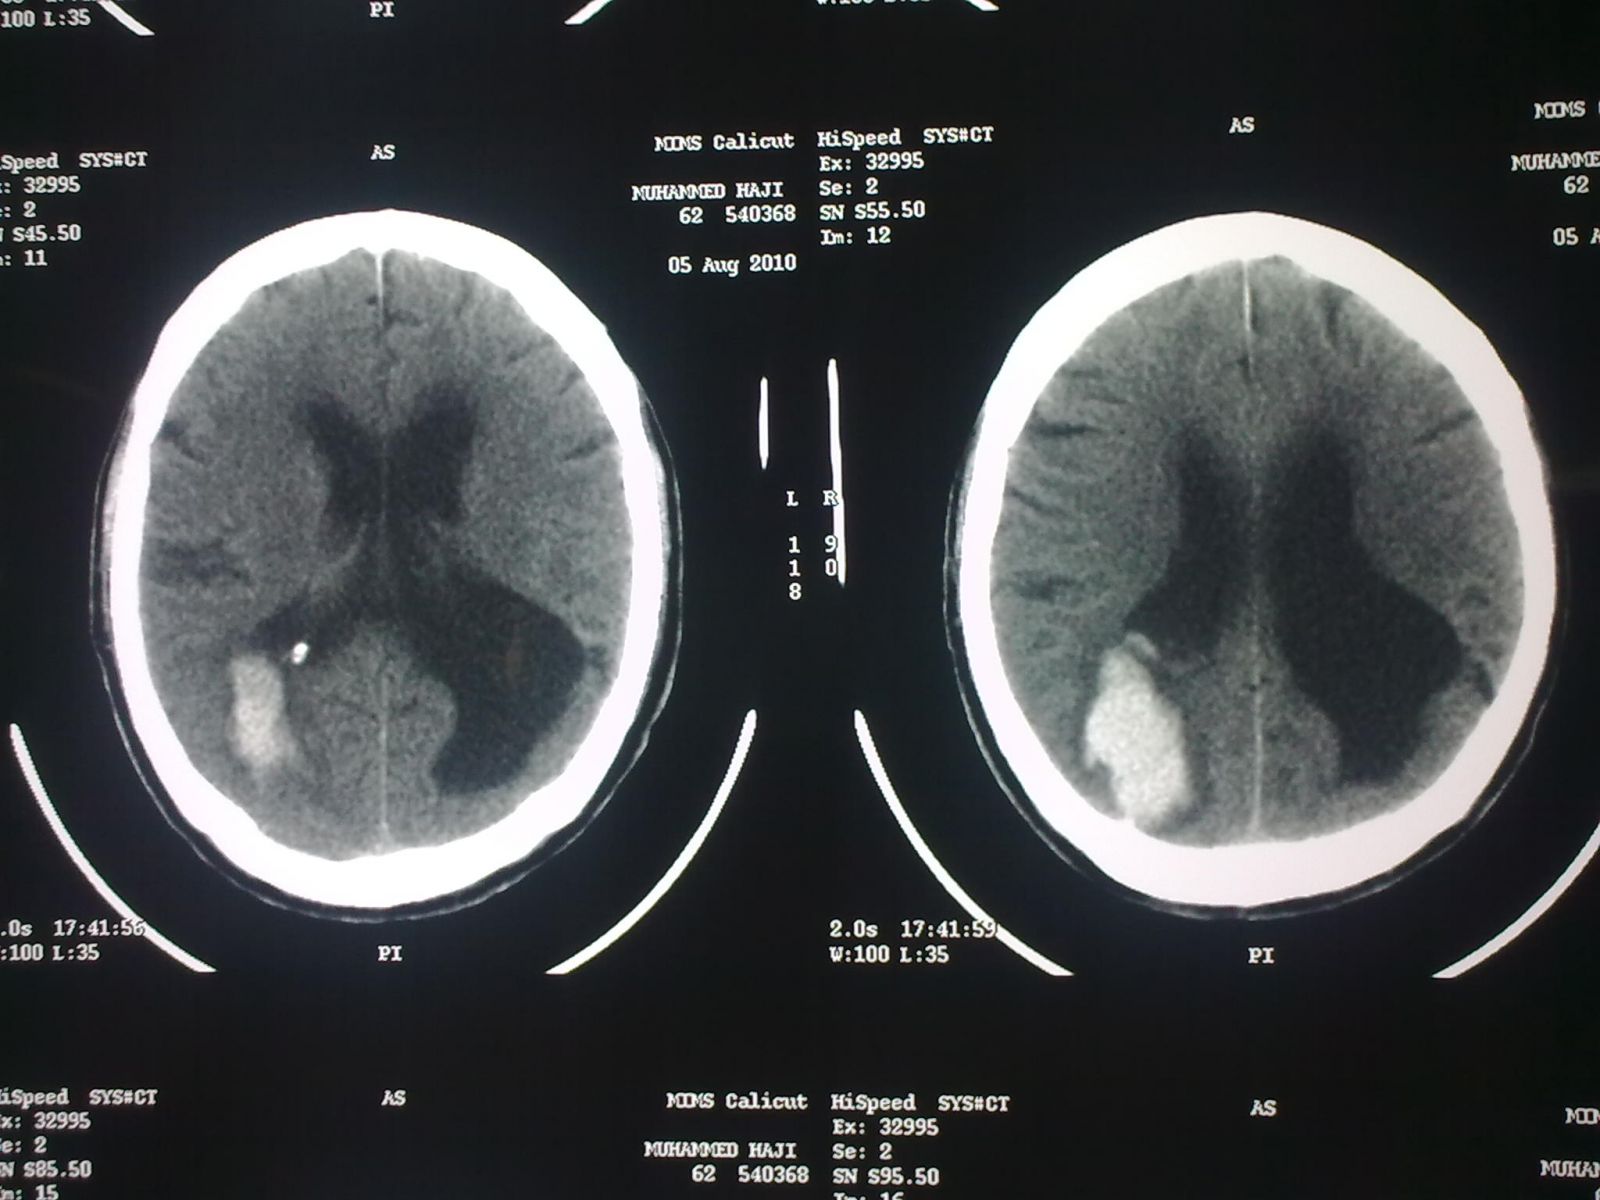

CT Brain(P): - Intracerebral bleed size 4.2cm * 2.8cm in the Rt. temporo-occipital lobe with

extension into Rt. lateral ventricle

- Mass effect with compression of occipital horn of Rt. lateral ventricle

- Hydrocephalus +

- Gliosis of Lt. occipital region with dialatation of Lt. lateral ventricle

- Bilateral ventricles are dialated

DIAGNOSIS: Intra-cerebral bleed Rt. temporo-occipital lobe with extension into Rt. lateral ventricles.